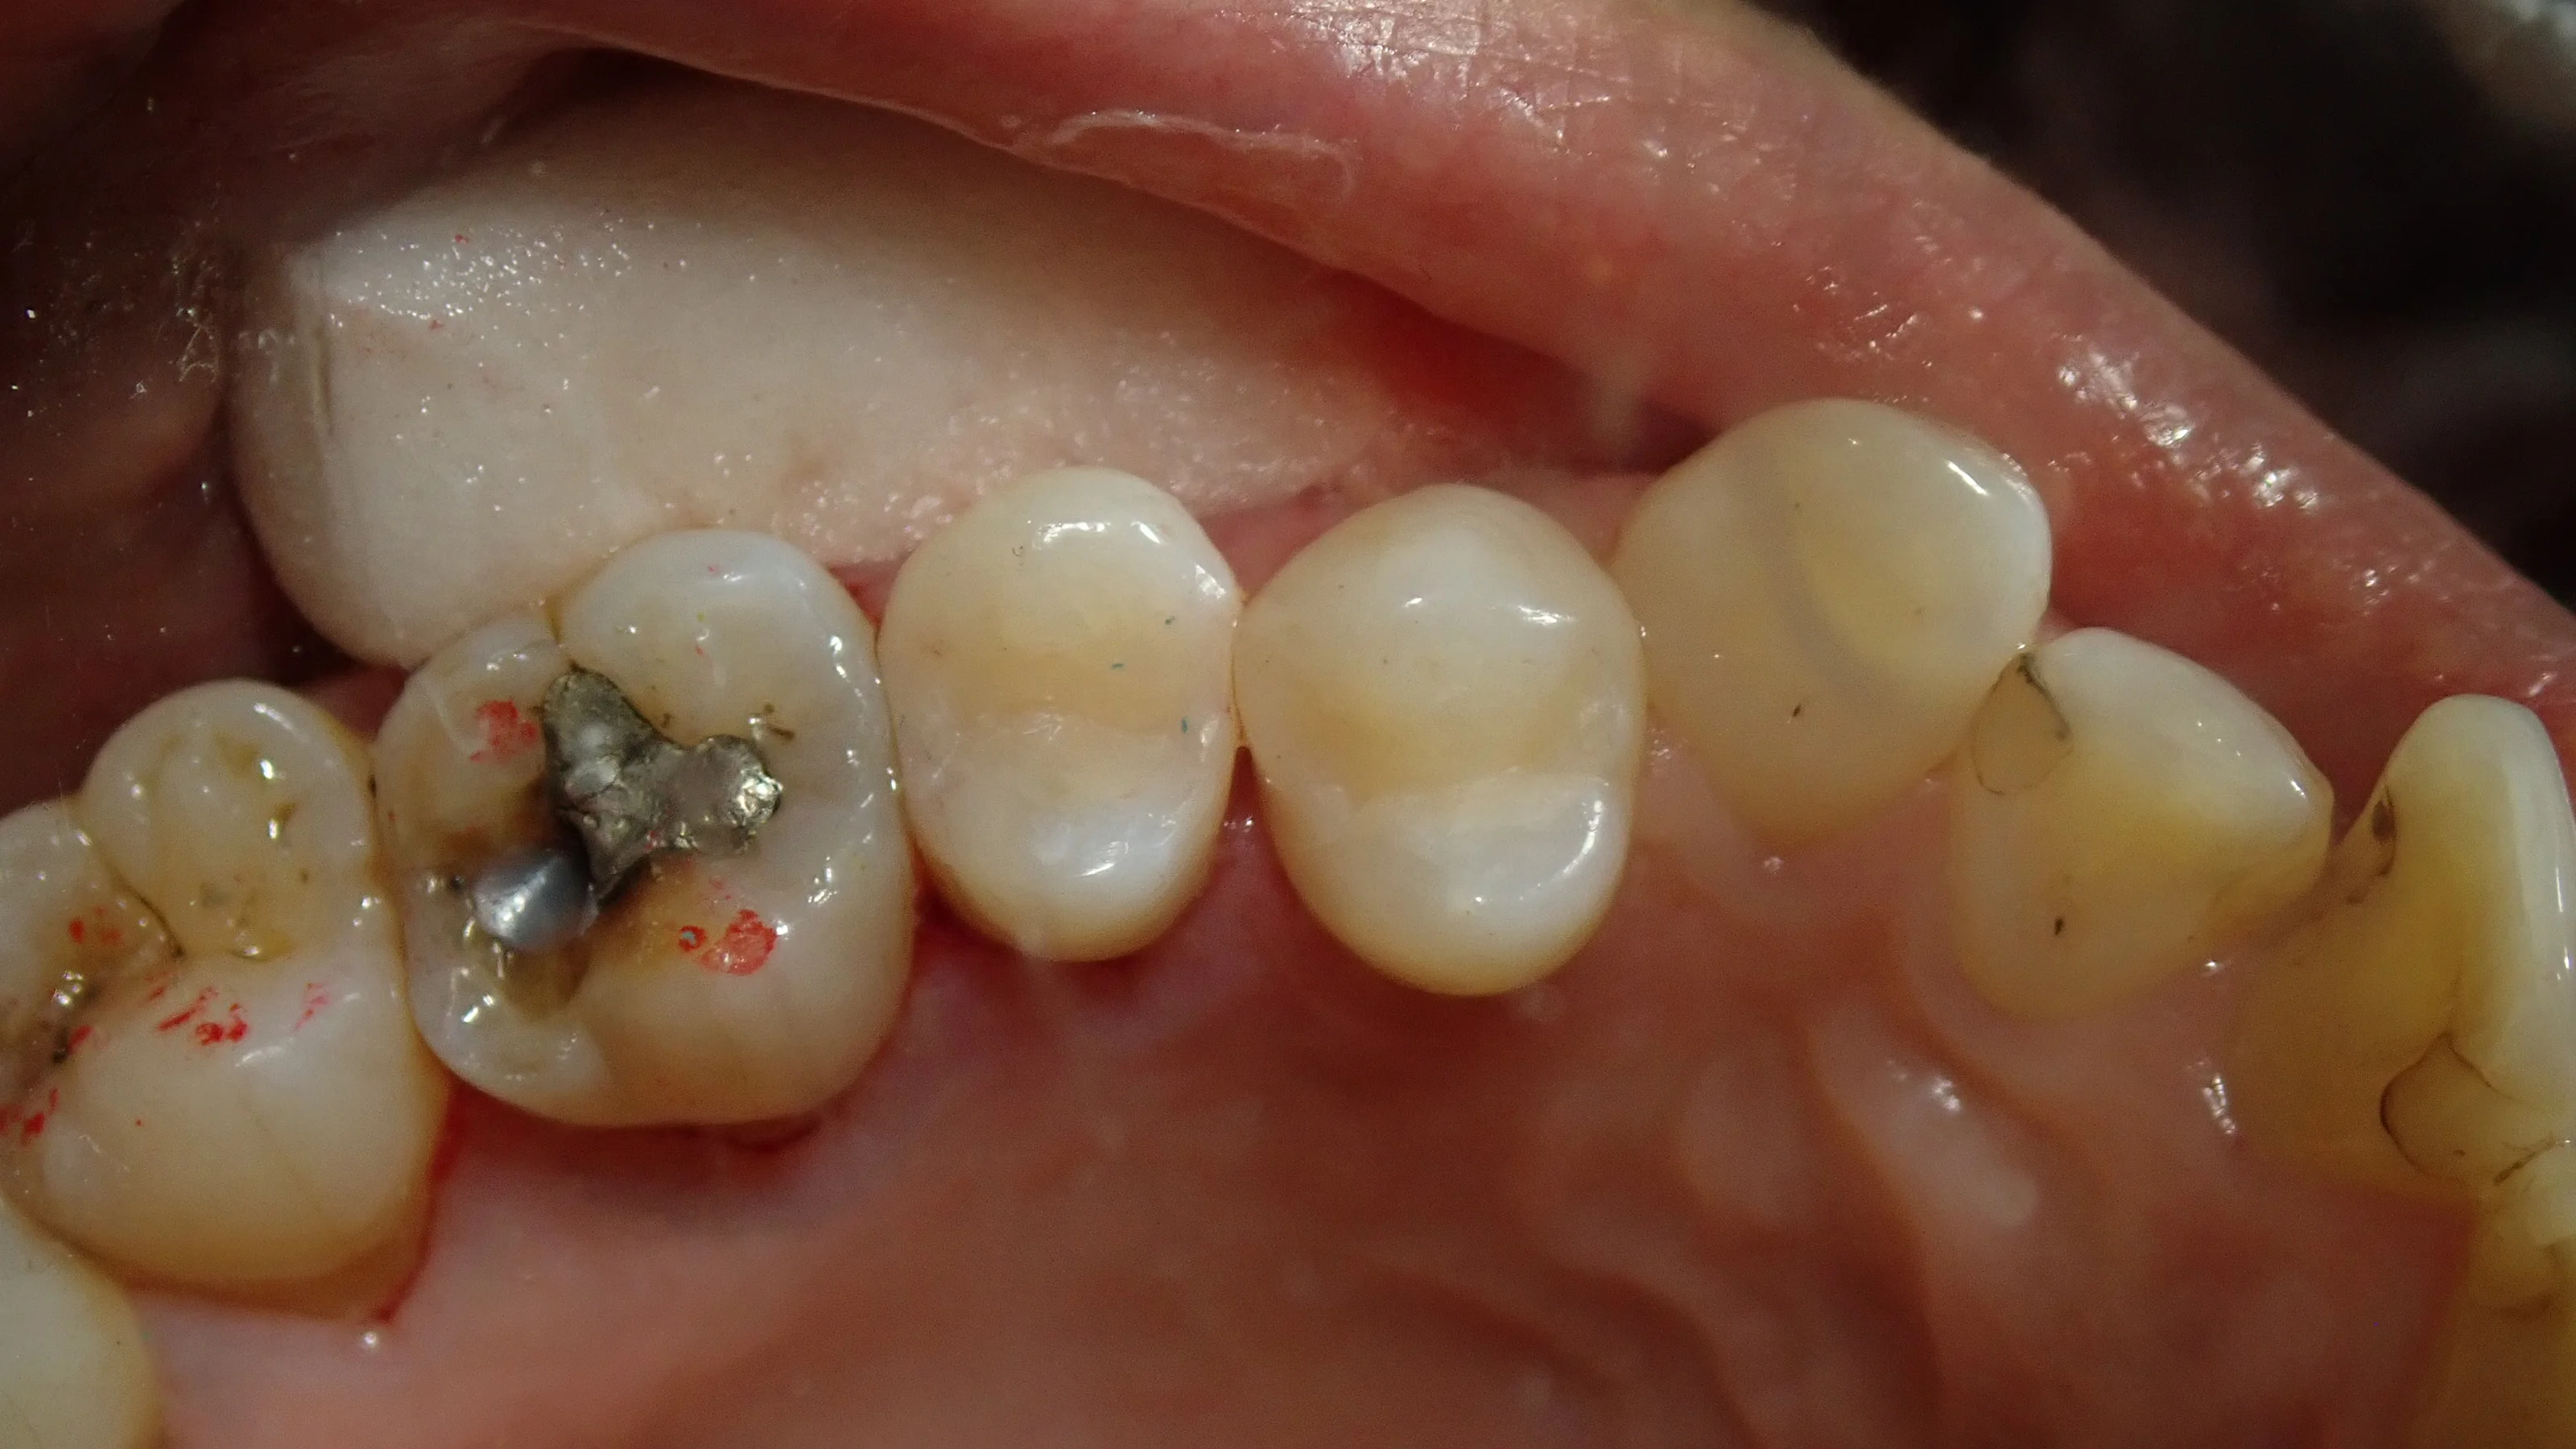

まずはいつもどおり術前から。

今回行うのは画面真ん中の2本の虫歯になります。

元々治療されている白い詰め物の中が黒っぽくなっているのが分かるかと思います。